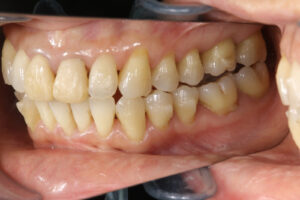

Invisalign correction failure

全く噛んでない

インビザラインで失敗した45歳女性

奥歯が噛んでいない

噛み合わせが悪くなった

歯の見た目は良くなったが、噛み合わせがずれて違和感がある。

食事のときに噛みにくくなる、顎が疲れる、痛むなど。